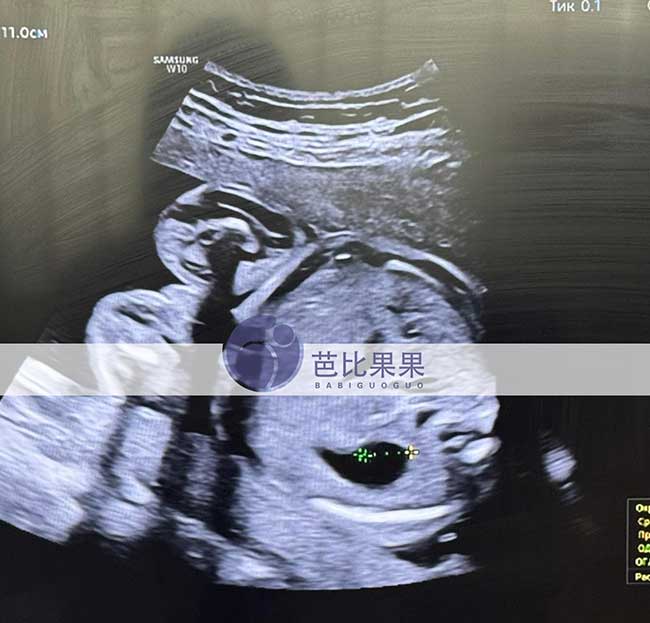

吴先生到乌克兰匹配的试管妈妈如期来做四维彩超啦!胎宝宝各项发育指标都稳稳达标,健健康康茁壮成长,每一次产检都是满心欢喜,静待可爱小天使平安到来。

吴先生到乌克兰匹配的试管妈妈如期来做四维彩超